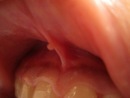

上唇小帯(じょうしんしょうたい)とは、上唇と歯茎(上顎の歯肉)をつなぐ細い帯状の粘膜組織です。この小帯は、口腔内の運動機能に関与し、唇の動きをサポートする役割を果たします。特に、幼児期の口腔発達において重要であり、授乳や発音の際に適切な機能を維持するために働いています。

上唇小帯の位置と発育過程

上唇小帯は、出生時には比較的長く、成長とともにその形状や位置が変化します。一般的には、乳歯が生え始める時期に小帯の長さや厚みが調整され、上顎前歯の発育とともに適切な形態へと変化していきます。しかし、一部の子どもでは、小帯が異常に短縮したり、過剰に発達したりすることがあります。